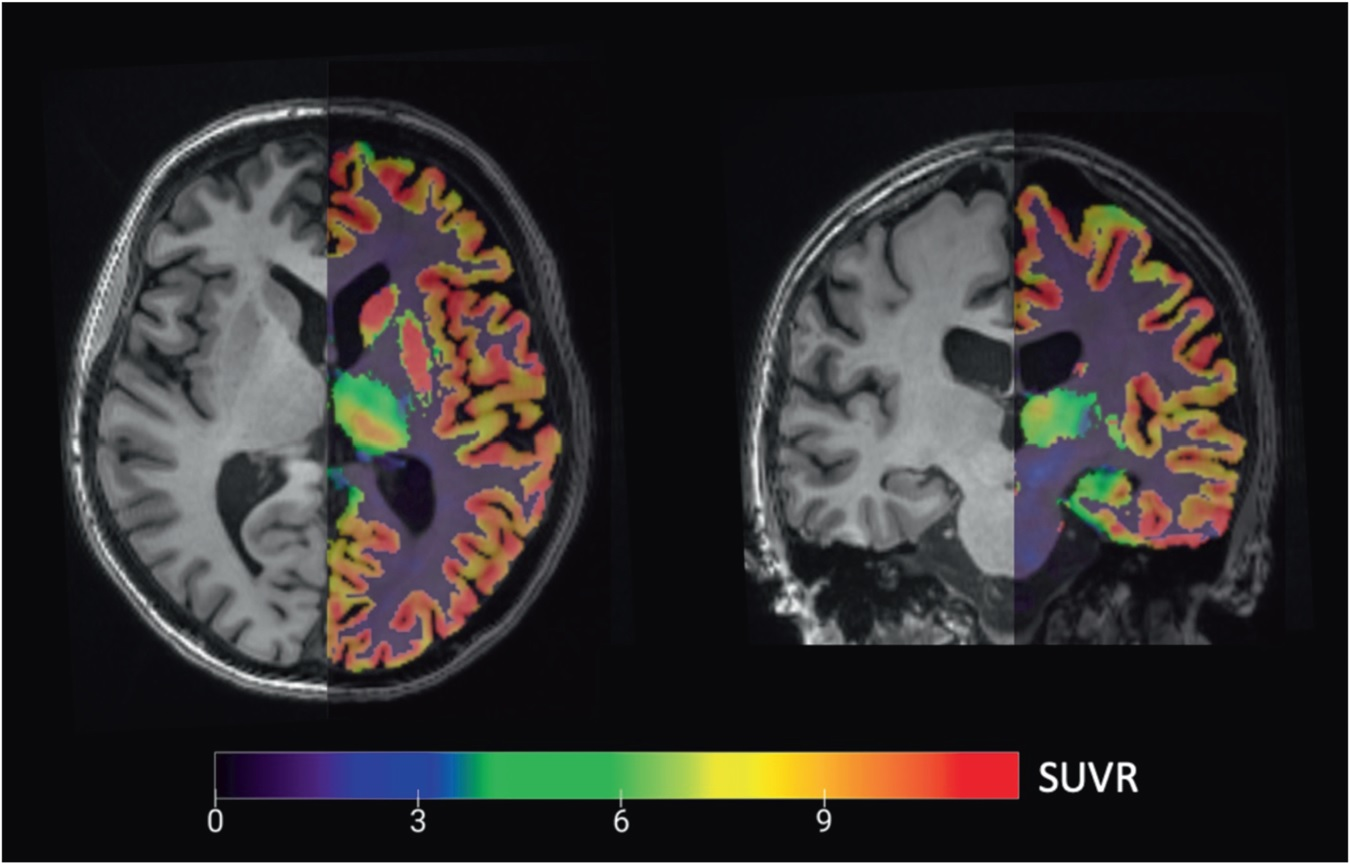

All participants received one injection of C-11 UCB-J (493 ± 224 MBq), with no significant difference in radioactivity or mass dose between groups. They also underwent high-resolution PET scans with C-11-labeled Pittsburgh Compound B (PiB) to detect beta-amyloid plaque, along with MRI scans and cognitive and neurologic evaluations. Results were based on C-11 UCB-J specifically binding to SV2A in the hippocampus, where neurodegeneration would be most prominent.

Their premise proved accurate. PET images showed that subjects with Alzheimer's disease had a significant reduction in hippocampal SV2A binding (41%), compared with cognitively normal participants. The reductions in binding remained significant even after the researchers corrected for brain atrophy.